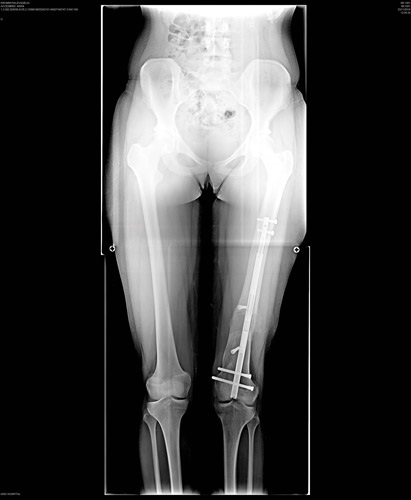

Το PRECICE® εμφυτεύεται χειρουργικά σε ένα ή περισσότερα οστά του κάτω άκρου (μηριαίο οστό ή κνήμη). Η επιμήκυνση (φωτογραφία 1) λαμβάνει χώρα όταν ο ιατρός ενεργοποιεί με μη επεμβατικό τρόπο τη μονάδα απομακρυσμένου ελέγχου που βρίσκεται ακριβώς επάνω στο εμφύτευμα. Το εσωτερικό εμφύτευμα χρησιμοποιεί τεχνολογία μαγνητών για την επιμήκυνση του οστού του άκρου μέσω μη επεμβατικού συστήματος απομακρυσμένου ελέγχου, το οποίο ρυθμίζει το εμφύτευμα εξωσωματικά.

Το εμφύτευμα PRECICE® κρατά τα οστά ενωμένα, έως ότου ο οργανισμός δημιουργήσει νέο οστό για την κάλυψη του κενού. Κατά τη φάση της σταθεροποίησης, το οστό αποκαθίσταται. Αφαιρείται από το μηριαίο οστό ή την κνήμη μετά το σχηματισμό ώριμου οστού (ο οποίος λαμβάνει χώρα συνήθως εντός 12 μηνών από την αρχική εμφύτευση) και την επίτευξη του επιθυμητού μήκους του άκρου